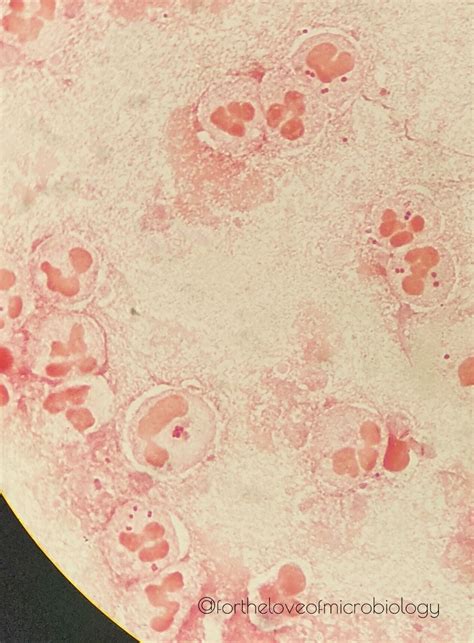

• Staining Properties: Due to their thin peptidoglycan layer, Gram Negative Diplococci do not retain the crystal violet stain used in Gram staining. Instead, they appear pink or red when counterstained with safranin or fuchsin.

• Gram Staining: This is the primary method for initial identification. Gram Negative Diplococci appear pink or red under the microscope after Gram staining.